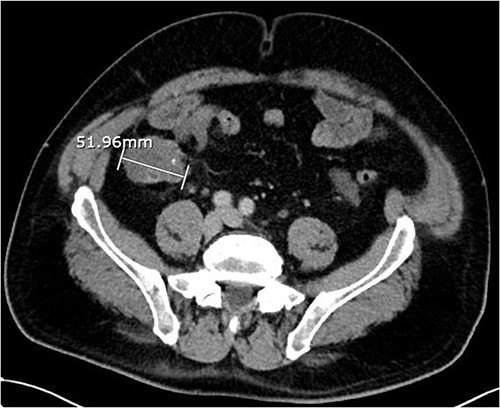

About 1 year later, the patient re-presented for anaemia and underwent a further CT scan. In the right iliac fossa, a 51.96 mm mass was noted such that the appendix could not be visualized separately, with a focus of calcification (Fig. 1). There was infiltration into the adjacent fat and abnormal soft tissue thickening of the peritoneal reflection along the right paracolic gutter. Multiple new peritoneal nodules in the upper abdomen were also identified (Fig. 2). The appearances were in keeping with disseminated malignancy. Following histological analysis, diagnoses of LAMN and PMP was made. The patient was initiated on mitomycin and capecitabine chemotherapy, which modestly reduced the size of the right iliac fossa mass from 51.96 mm to 44.23 mm (Fig. 3).

Axial CT abdomen with contrast demonstrating a peritoneal deposit posterior to the descending colon in the left iliac fossa, measuring 37.15 mm.